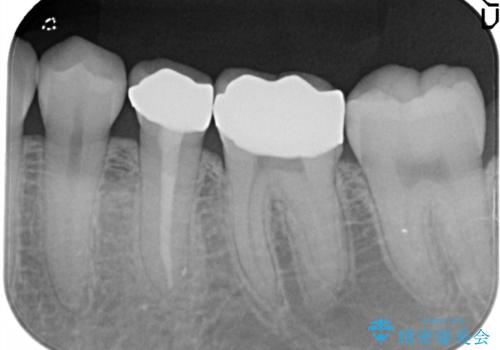

【メタルフリー】銀歯を白くしたい。オールセラミッククラウン。

- 銀歯を白くしたいと希望され来院されました。

すぐにでも白くしたいとのことで、2回目の来院で銀歯を白い仮歯に変更し喜んでいただきました。

根管治療は林先生に依頼しております。

ただ単純に白くするでけではなく拡大鏡を使用し、丁寧な処置を行なっております。